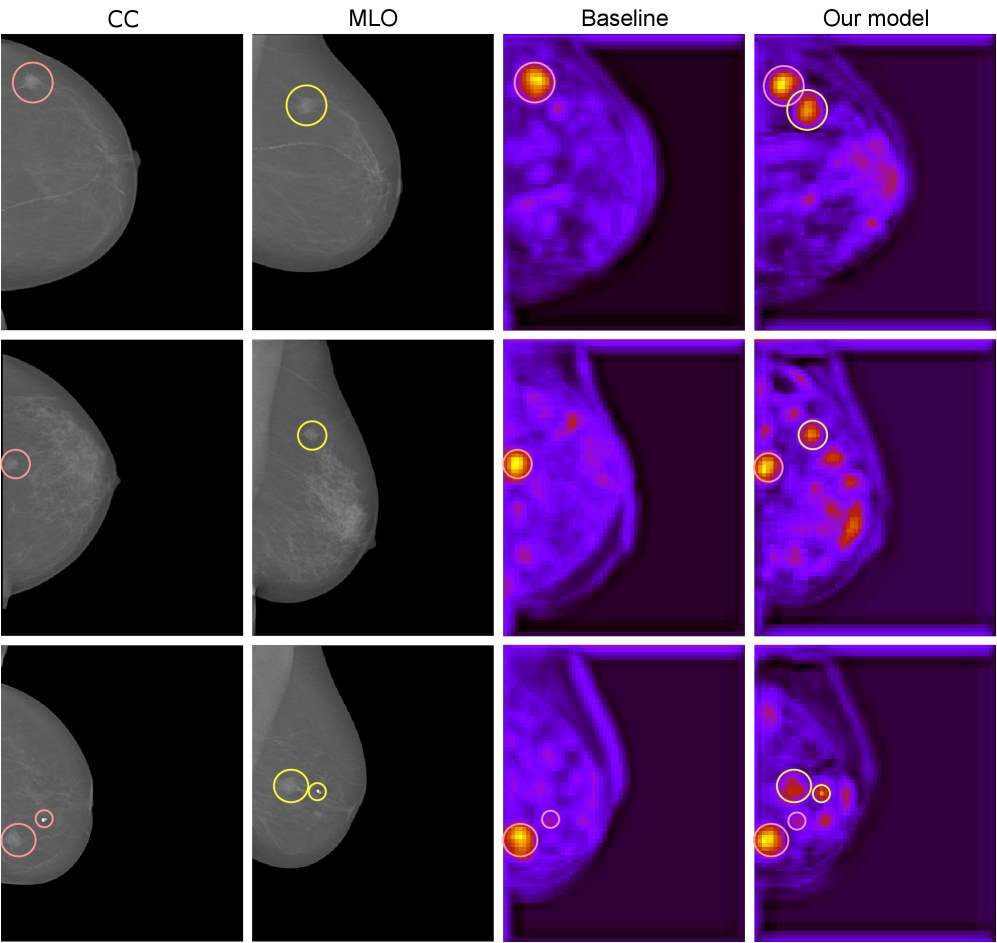

Figure 1: Visualization of hypercomplex multi-view learning in breast cancer classification. Malignant masses are highlighted in red and yellow in the respective views (CC and MLO). We compare activation maps of a real-valued baseline (SEnet) and our hypercomplex model (PHYSEnet). The proposed method learns from both views as shown by the highlighted areas corresponding to both views, while the conventional model focuses only on one view, discarding the information coming from the second one.

We provide a visualization of how multi-view hypercomplex learning works utilizing simple activation maps in Fig. 1 and established explainability techniques, i.e., Grad-CAM [75] and saliency maps [76] in Fig. 8. From these visualizations, it is clear how the hypercomplex model learns from both views as the most important areas of the explanations correspond to the ROI in the two views. On the contrary, the real-valued network seems to overfit on the CC view, which is indeed a typical behavior encountered in the literature [22]. Moreover, these visualizations serve as a form of weakly supervised detection, highlighting regions that contribute to the model’s classification decisions.

Refer to caption

Figure 8: Saliency (top two) and Grad-CAM maps (bottom two) of SEnet and PHYSEnet from different patients. Circles indicate malignant masses, while red and yellow correspond to the CC and MLO view, respectively. Observing the highlighted areas, it is visible that the hypercomplex network effectively models the multi-view information contained in the two views, unlike its real-valued counterpart.